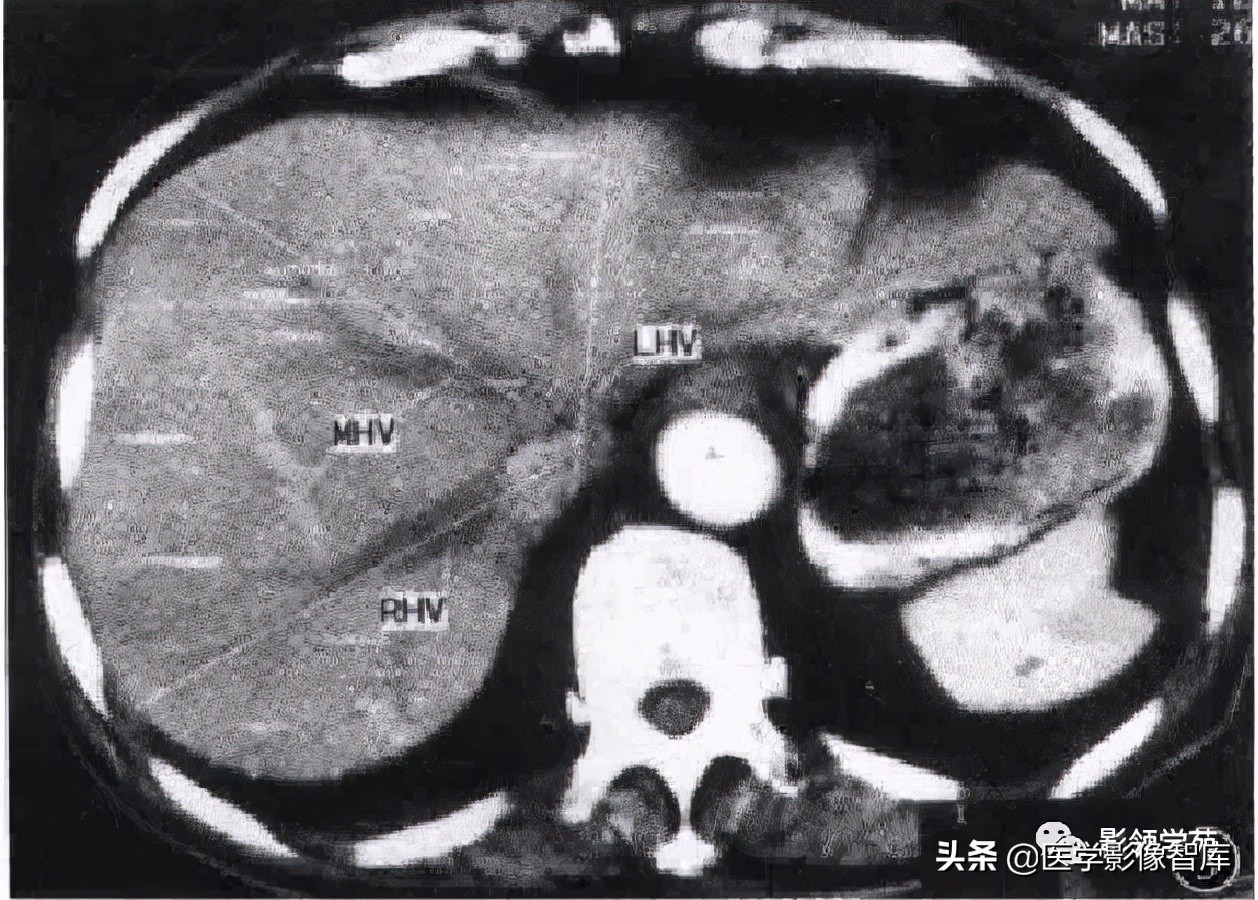

第二肝门:位于肝脏的膈面顶部,是肝左、中、右静脉汇入下腔静脉处。

3支主肝静脉将肝分隔成4个部分。

左、中、右3支主肝静脉走行区所形成的纵形切面(称为肝静脉裂)将肝分隔成4个部分,称为四个扇区。

第二肝门下方层面CT横断面